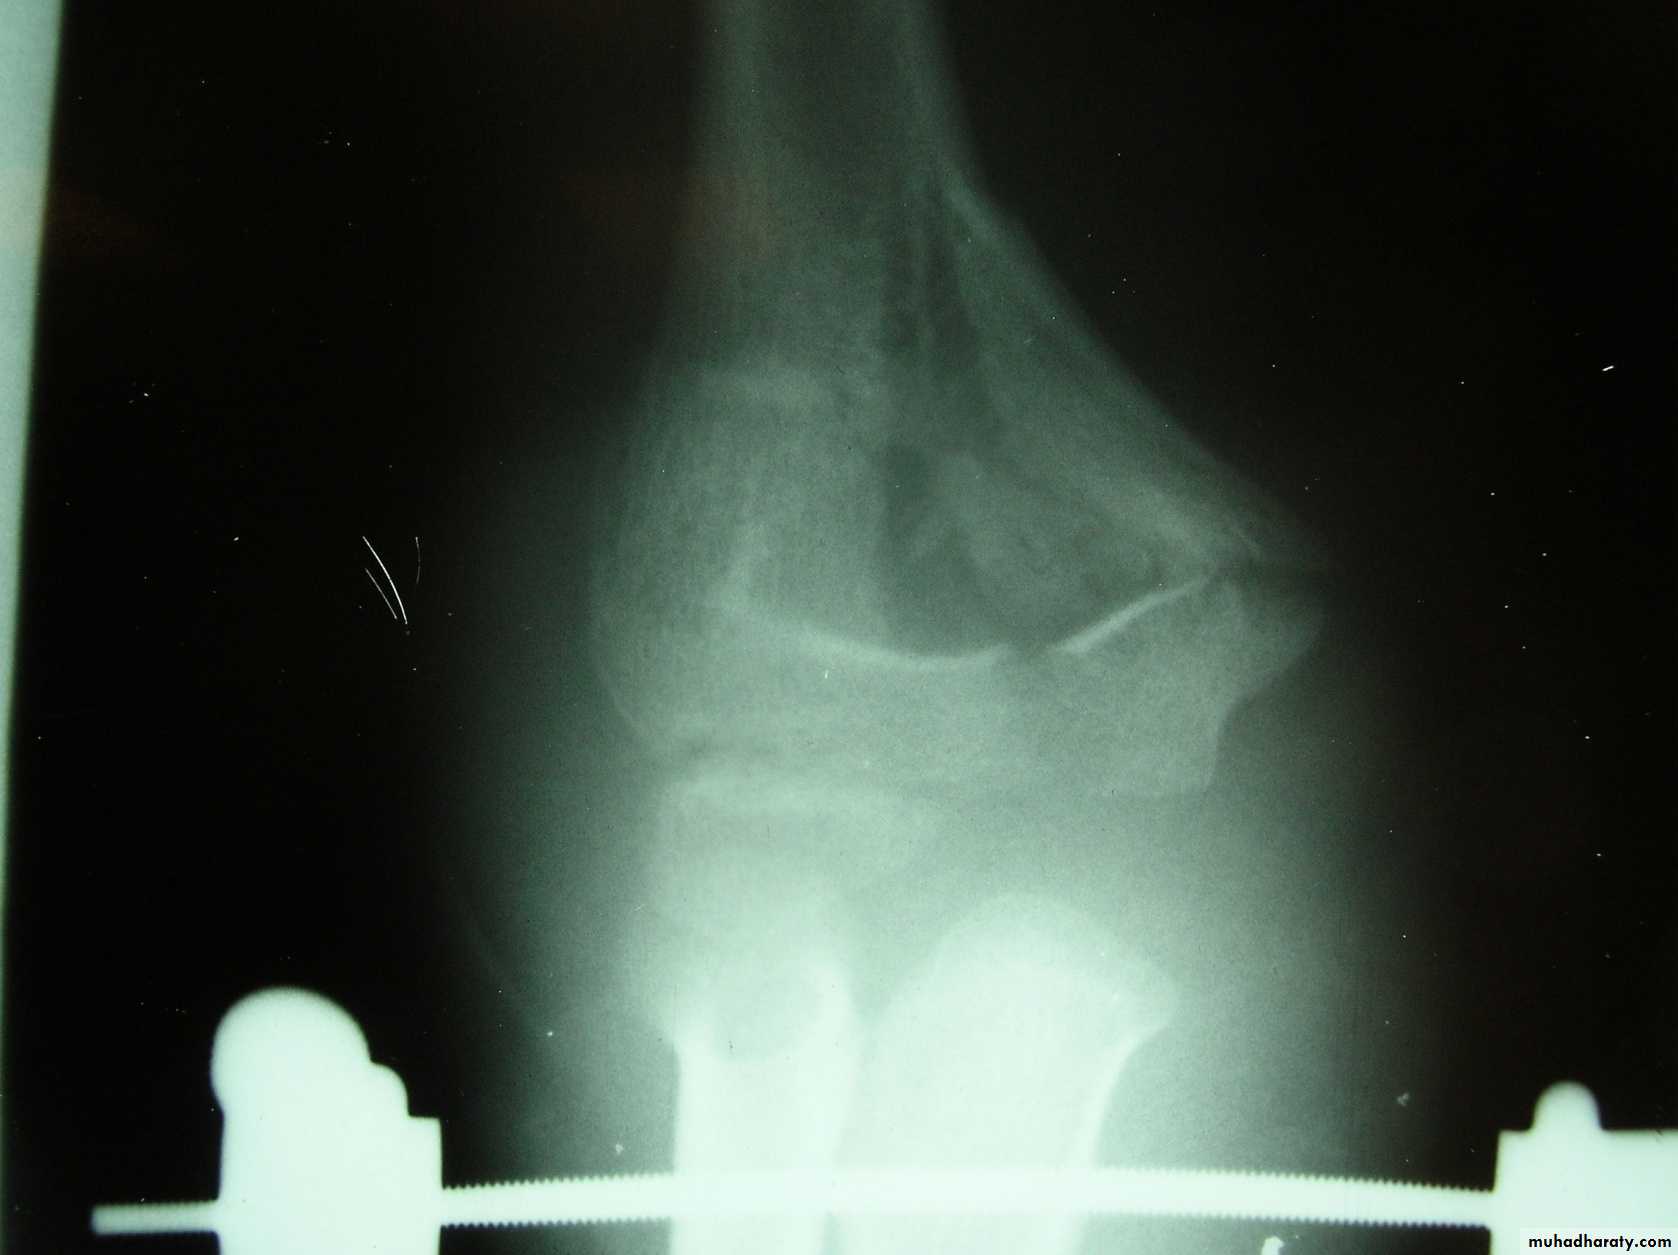

This classical Type III pattern

is obviously a flexion injury.With these one needs to be

prepared to do an open reduction !!

8 y.o.

Is this a simple extension

type supracondylar fracture ??

It also has

anterolatateraldisplacement !!

The distal fragment is

not flexed,but also it is not extended to any degree.

This also is a Type III Flexion Pattern.

What is differentabout this fracture?

But, if not recognized as such, it may be a problem.

This fracture was irreducible,

and required an open reduction !!!